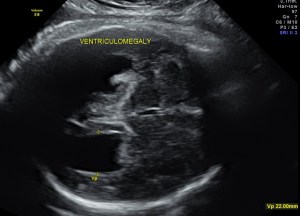

This was a 30 year old primi gravida with no history of consanguinity . This was referred for evaluation of suspected ventriculomegaly.

prominent ventriculomegaly of posterior horns of both lateral ventricles – colpocephaly